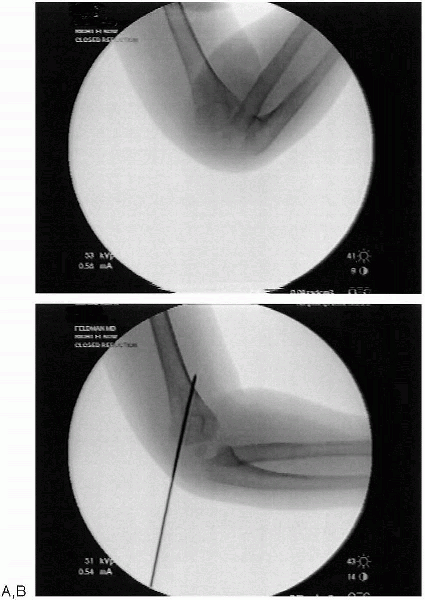

FIGURE 12-8. A: Lateral translation of supracondylar humerus fracture. B: Post reduction in extension (right elbow).

Correction of medial/lateral displacement. Medial

or lateral translation is corrected by applying a translational force

with or without a valgus or varus moment in the coronal plane to the

distal fragment. Confirmation of fragment placement is achieved with image intensification with the elbow in extension. Minimal traction is used to achieve this reduction (Fig. 12-8). -